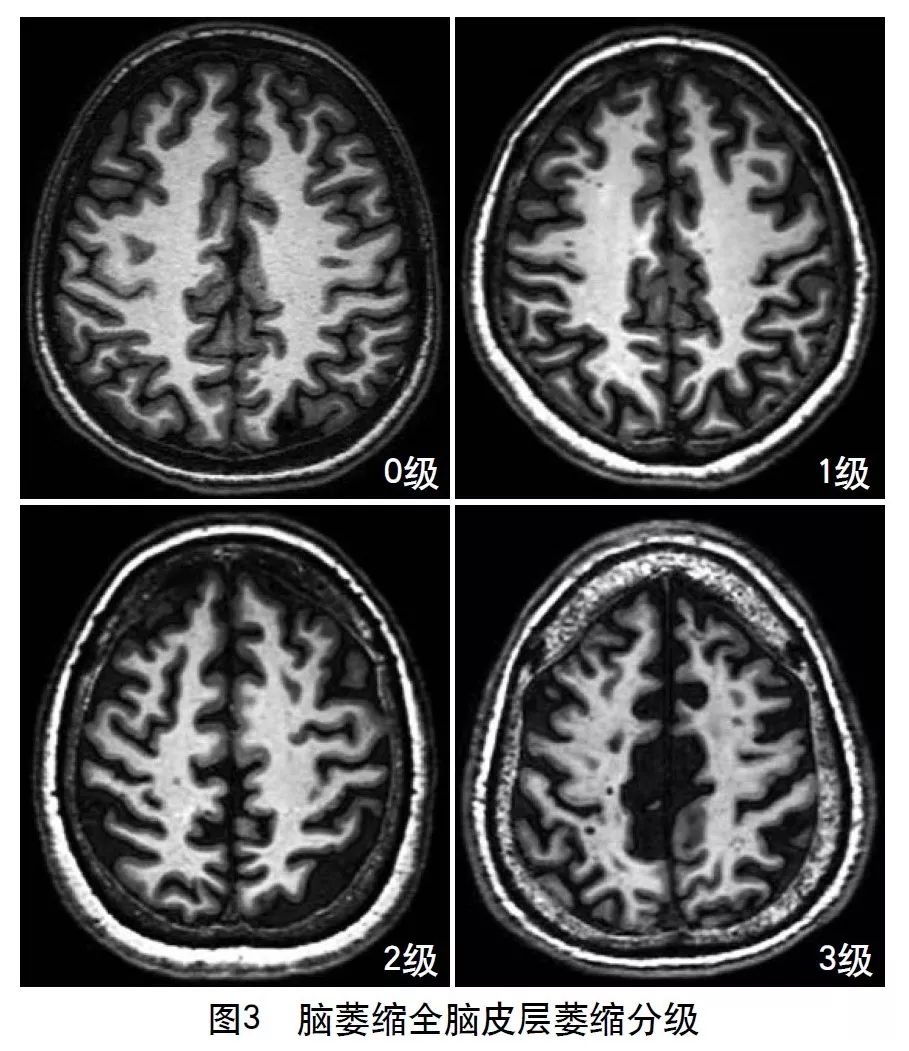

2013年的共识指南将脑萎缩定义为与特定的局灶性损伤,如脑外伤或脑梗死无关的脑容积减少。脑萎缩可以是广泛的或局部的(如特定的脑叶或海马等特定区域),可以是对称或不对称的,亦可以是策划选择性的(如发生在白质等某一特定策划层)。目前不同部位的脑萎缩有相应的诊断标准,全脑皮层萎缩分级用于评价全脑(图3);内侧颞叶萎缩分级主要评价颞叶内侧,重点是海马(图4);Koedam分级主要评价顶叶,尤其是扣带回和楔前叶(图5);Kipps/Davies分级主要评价额颞叶(图6)。推测脑策划减少是由脑沟(周围)和脑室(中心)的脑脊液空间相对于颅内容积扩大所引起的。